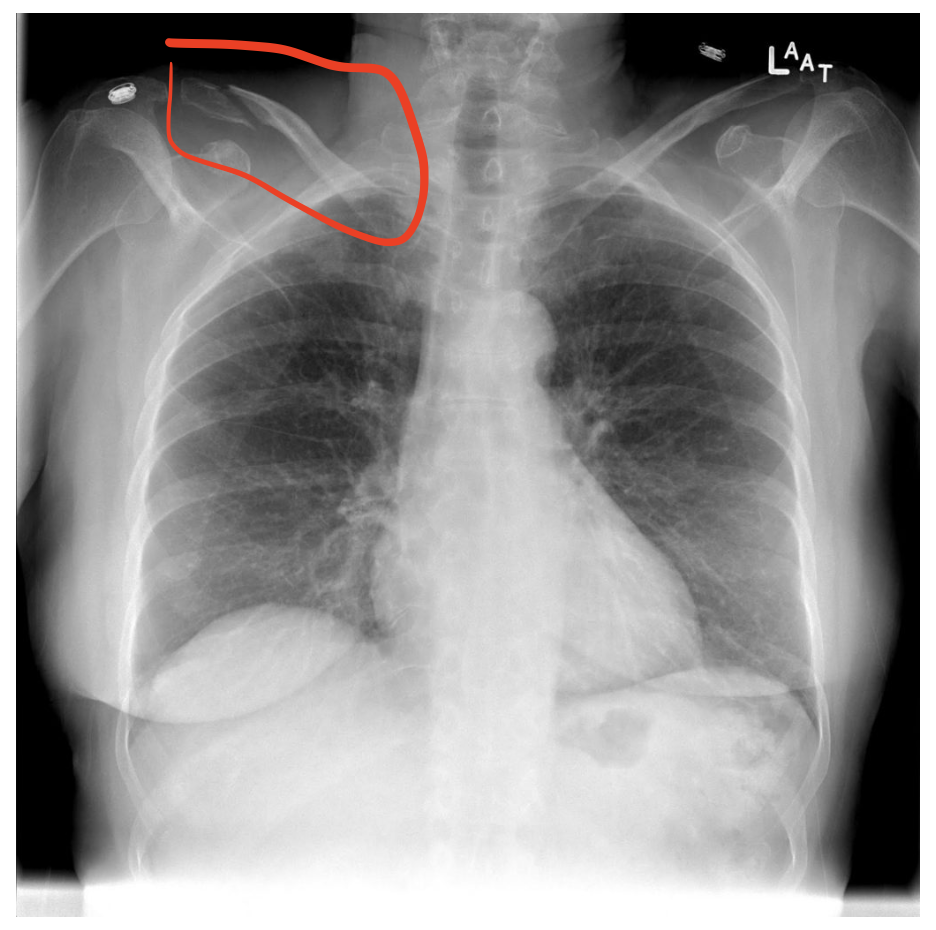

2. Bones (뼈)

뼈를 확인하기 위해선 별도의 x-ray 프로토콜이 존재하지만, 흉부 x ray에서도 기본적인 뼈의 모양과 위치는 확인할 수 있기에, 보이는 뼈에 이상은 없는지 눈으로 확인할 필요가 있다.

양측 clavicle(빗장뼈), Ribs(갈비뼈), humerus(상완골)과 scapula(견갑골)의 일부, 그리고 가능하다면 verterbra body(척추뼈)의 기본적인 이상 여부를 확인한다.

하지만 필자의 생각으론 각 뼈를 좀 더 정확하게 보기 위한 x ray 프로토콜들이 존재하므로, 뼈를 평가하기 위해서는 chest x ray가 아닌 좀더 특화된 x ray를 촬영할 필요가 있다 생각한다.